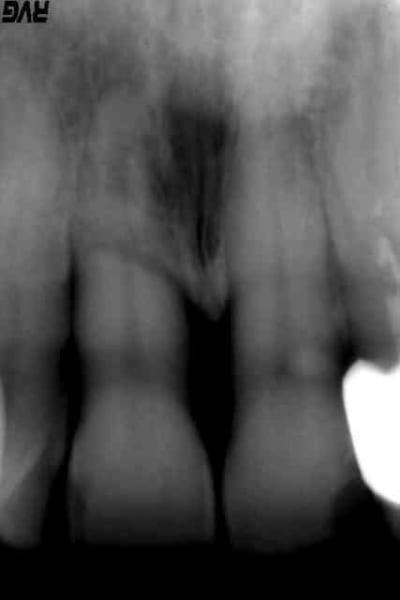

patiente 45 ans, pas de pb médicaux particulier, hygiène presque correcte, se présente ce matin au cabinet pour mobilité de 11 avec sensibilité au froid et au chaud depuis 10 jours.

Examen clinique : mobilité de 11 marquée, sensibilité à la mobilisation, hypersensibilité au froid. Leger trauma occlusal, pas de choc récent sur la dent.

Examen radio : voir PJ, on dirait outre un pb paro évident, une fracture de la racine au niveau de l'os alvéolaire mais pourquoi? L'endodonte semble bizarre au delà de l'os...

Abrasion 13 et surtout 43 très évoluée, possible prédominance proprioceptive antérieure par défaillance post.

tartre profond

abrasions -->bruxisme

hygiène très perfectible

tabagie?